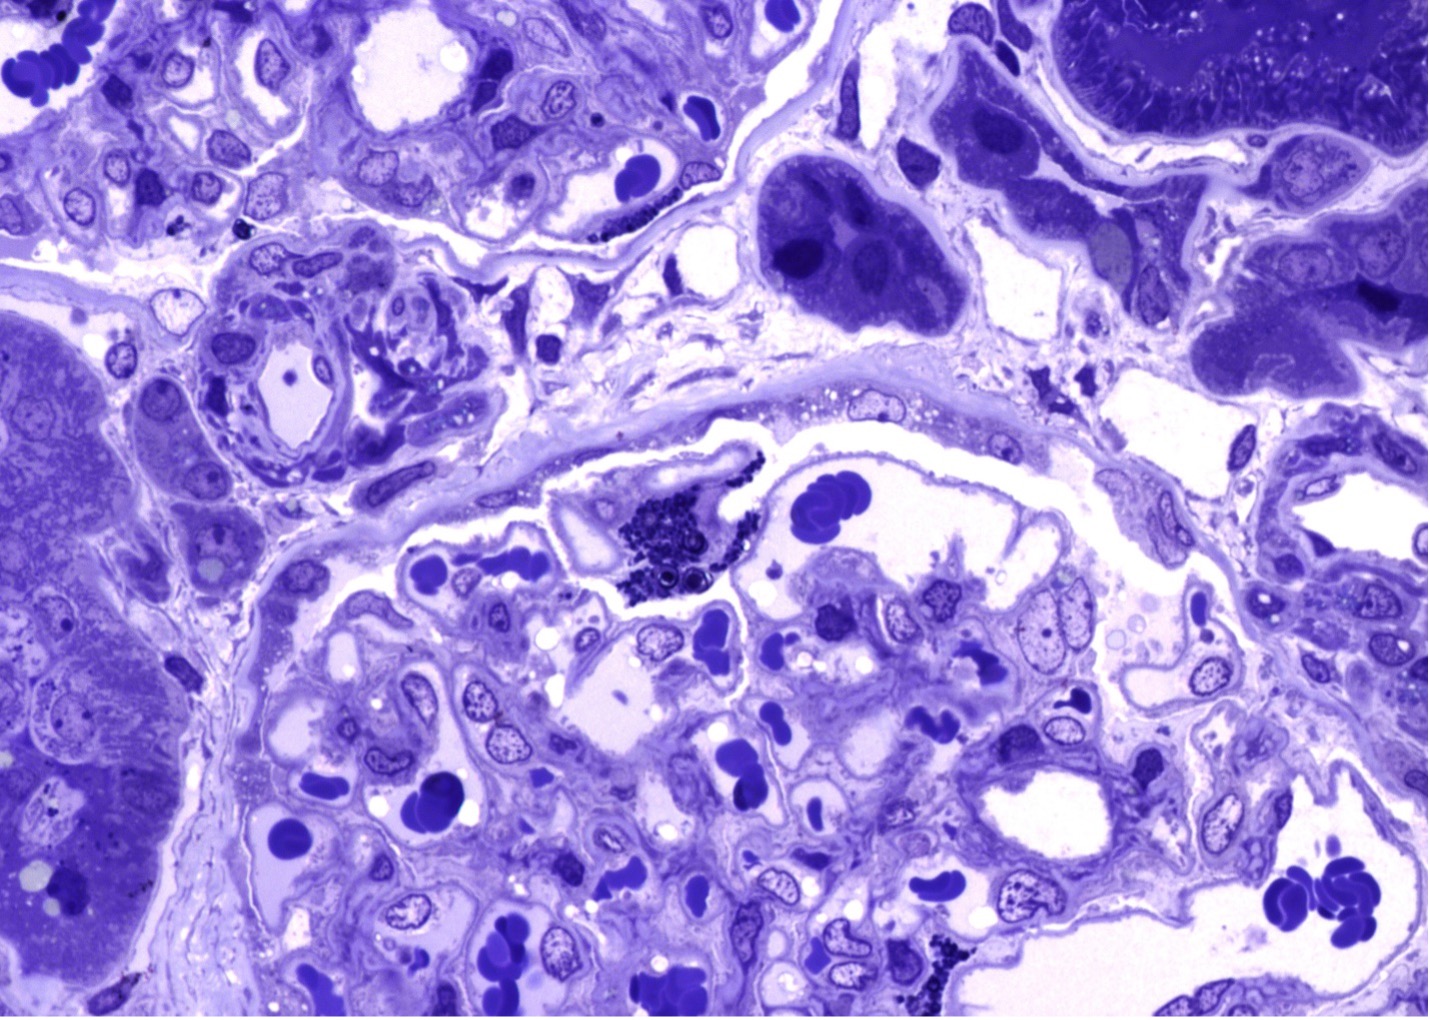

Figure 2 (Microscopic Photo, 400x) Segmental podocytes have prominent and expanded cytoplasm with round blue cytoplasmic droplets (arrows, toluidine blue stained one-micron thick sections).

Kidney biopsy pathologic findings by light microscopy (LM) and electron microscopy (EM) are quite characteristic in Fabry disease. LM shows visceral glomerular epithelial cells (podocytes) and distal tubular epithelial cells with expanded cytoplasm and a marked foamy appearance (vacuolization), most prominent on the trichrome stain and seem as blue inclusions on toluidine blue stained plastic embedded LM of the EM specimen10. EM reveals podocytes that have prominent and expanded cytoplasm that contains numerous rounded electron-dense lipid inclusions (myelin figures, aka zebra bodies). Myelin figures or zebra bodies represent deposits of Gb3 primarily within enlarged secondary lysosomes as lamellated membrane structures11. These inclusions, composed of concentric layers with a periodicity of 3.5 to 5 nm and often an onion skin appearance, are considered a hallmark of glycolipid storage disorders12. These lipid inclusions may be seen in all glomerular cell types (most prominently podocytes), arteriolar smooth muscle cells, and tubular cells (mostly distal tubules) 11. Podocyte foot process effacement may range from focal to diffuse. Immunofluorescence staining does not typically contribute to the diagnosis but may be useful in excluding other coincident kidney disorders.